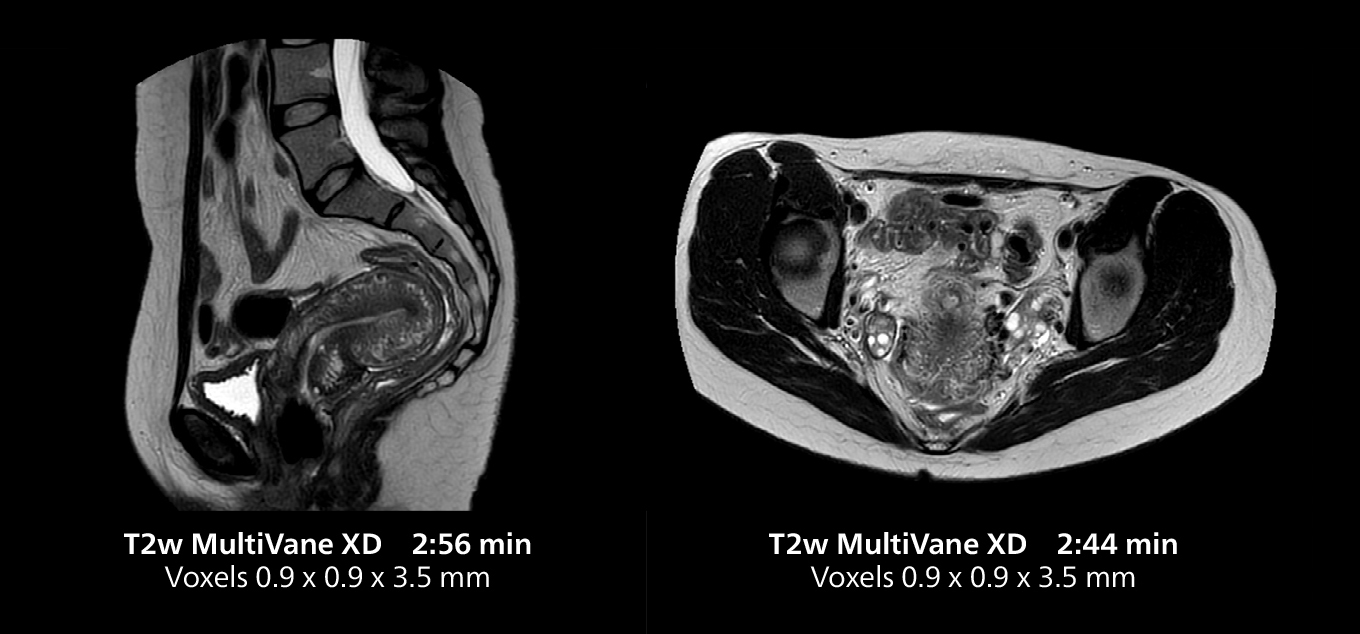

Dr. Gellée highlights the robust free-breathing scans as “the feature that makes the biggest difference in my daily work. The 3D free breathing sequences are very reproducible, and the axial acquisition is very good. For example, in endometriosis, which is one of my focus areas, it provides high contrast and good resolution so that I can see small details. We also use free breathing for liver and pancreas imaging. In multi-phase liver studies, 4D Free Breathing delivers 3-second temporal resolution, making a dynamic scan with more than one arterial phase possible.”

This MRI case illustrates good resolution and imaging quality obtained within reasonable scan times using the MR 5300 1.5T system with the anterior torso cardiac coil that allows use of a large field of view (FOV).